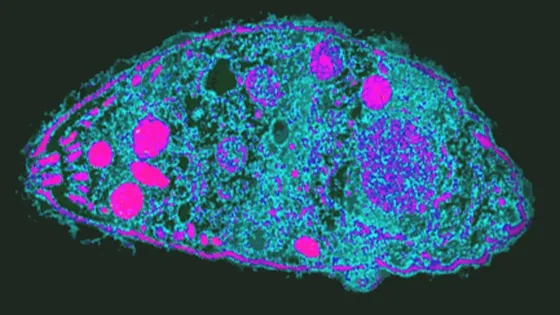

- Toxoplasma gondii - паразит, который живет в мозге десятилетиями и меняет поведение зараженных клеток.

- Ученые из Калифорнийского университета в Риверсайде исследовали этот паразит и обнаружили ключевое отличие зараженных клеток.

- Зараженные клетки выделяют меньше внеклеточных везикул (ВВ), которые участвуют в передаче сигналов между клетками и могут быть маркером скрытой инфекции.